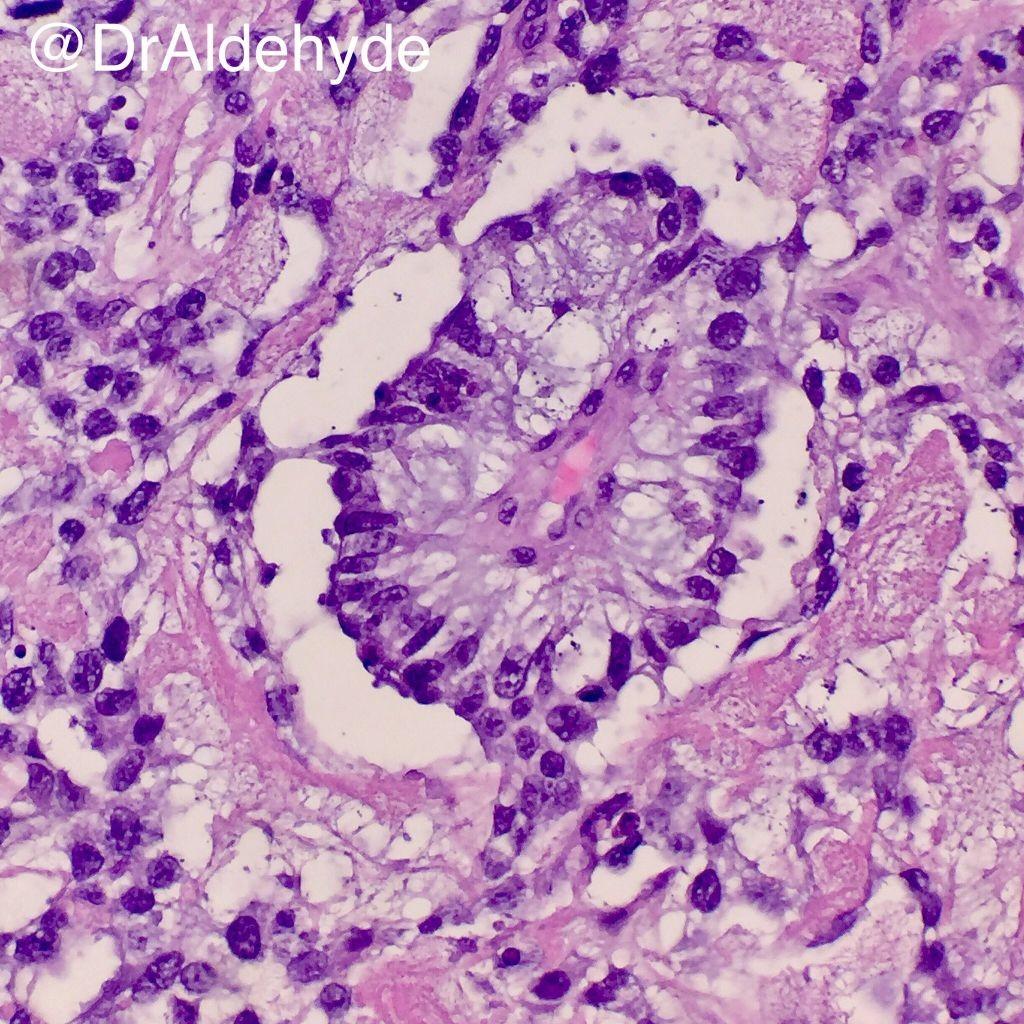

Yolk sac tumor (Endodermal sinus tumor)

Account for about 10-20% of malignant germ cell tumors

AFP is tumor marker

Rapid progression can be noted

Commonly diagnosed at stage I but due to poorer prognosis all patients are offered chemotherapy